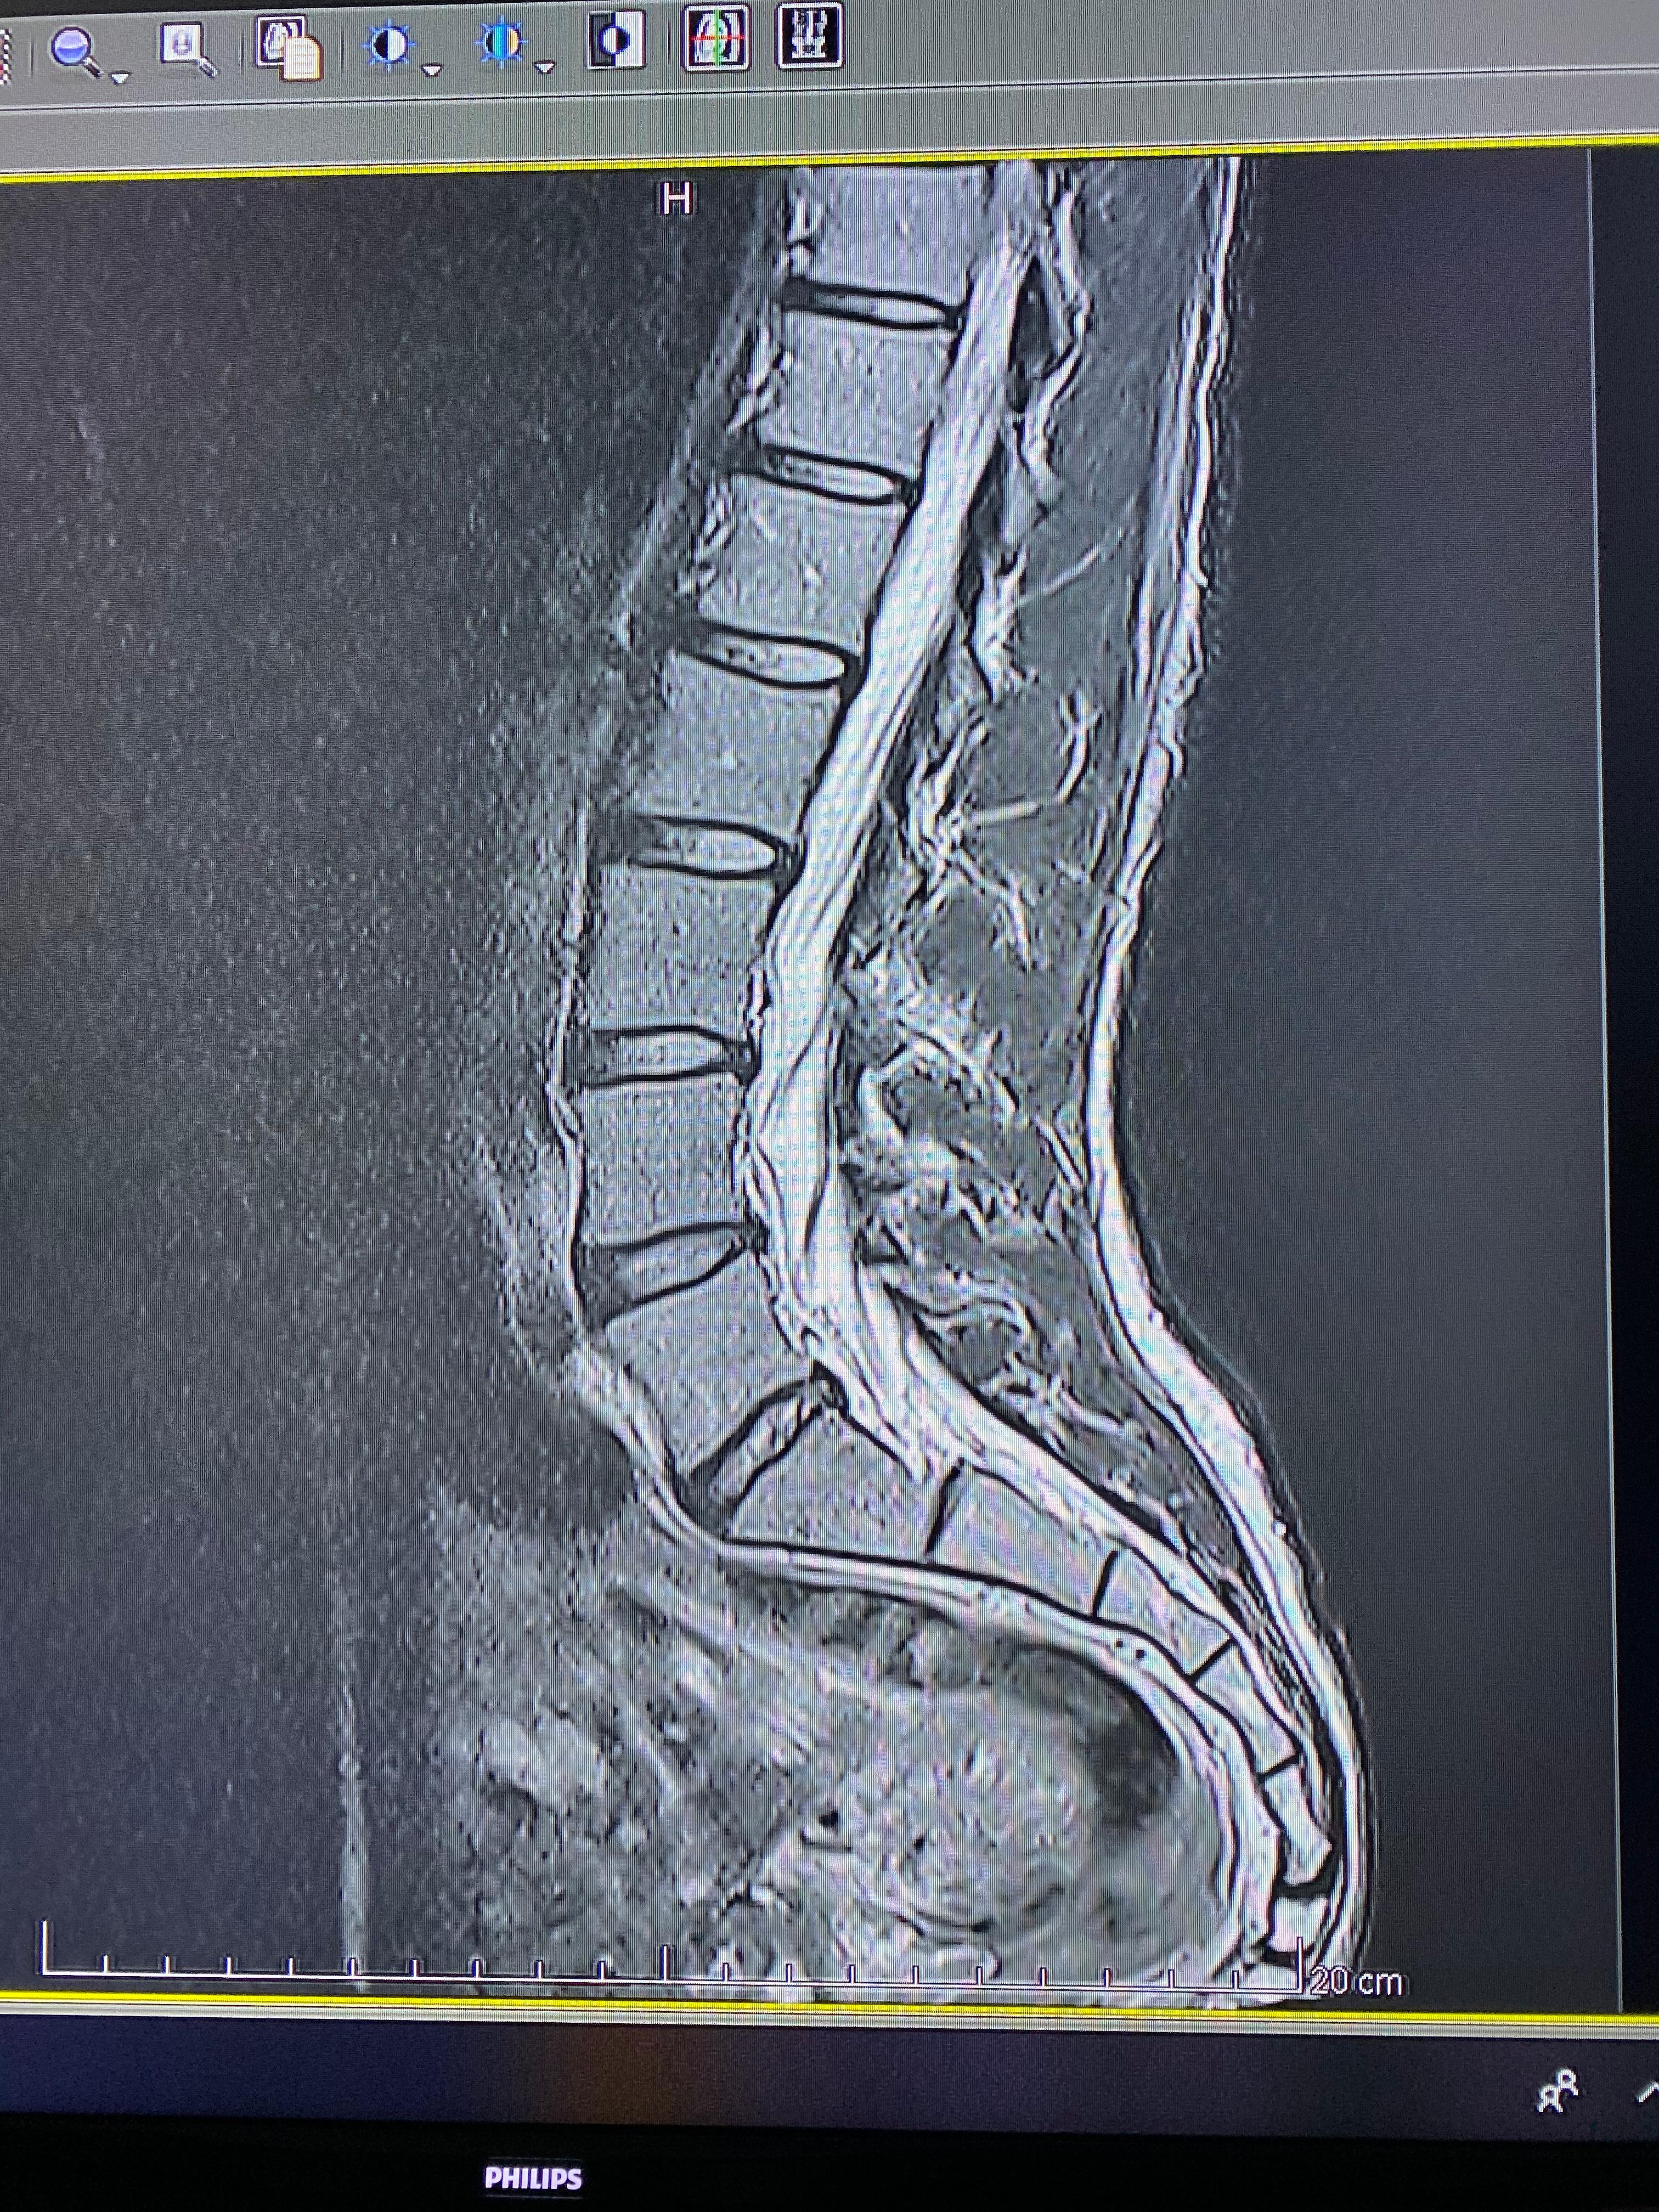

MRT Bilder LWS erste Einschätzung?

Wer kann mir etwas zu meiner LWS sagen? (Bandscheibenvorfall, MRT Befund)

Wer kann mir diese MRT Aufnahmen der LWS auswerten ? (Wirbelsäule, Befund)